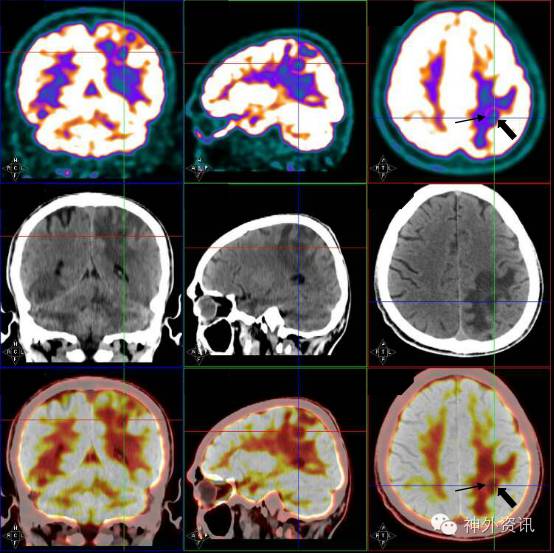

患者1月前无明显诱因下出现头胀嗜睡,伴记忆力下降,查头颅MRI提示:两侧大脑、小脑半球多发占位,环形强化,伴周围水肿,考虑转移性肿瘤(图1a-e)。

经专科医院感染科医生会诊后,根据脑部MRI增强检查显示特点,诊断考虑“弓形体脑病”。即行血和脑脊液弓形虫抗体检查,并启动磺胺类药物治疗。虽然患者血清和脑脊液检查结果阴性,但治疗2周后患者头颅增强MRI复查提示大部分病灶消失,左侧顶叶和小脑病灶明显缩小(图1 f-j)。病人症状也有明显好转。结合MRI影像学特点及临床治疗效果,最后诊断考虑为“AIDS继发弓形体脑病”。目前在继续治疗及随访中。

图1. a-e:治疗前头颅MRI可见患者左侧顶叶,右侧枕叶,双侧颞叶及小脑多发占位,环形强化,周围可见水肿暗带;f-j:磺胺类药物治疗2周后,见左侧顶叶和小脑病灶明显缩小,其余病灶基本消失。